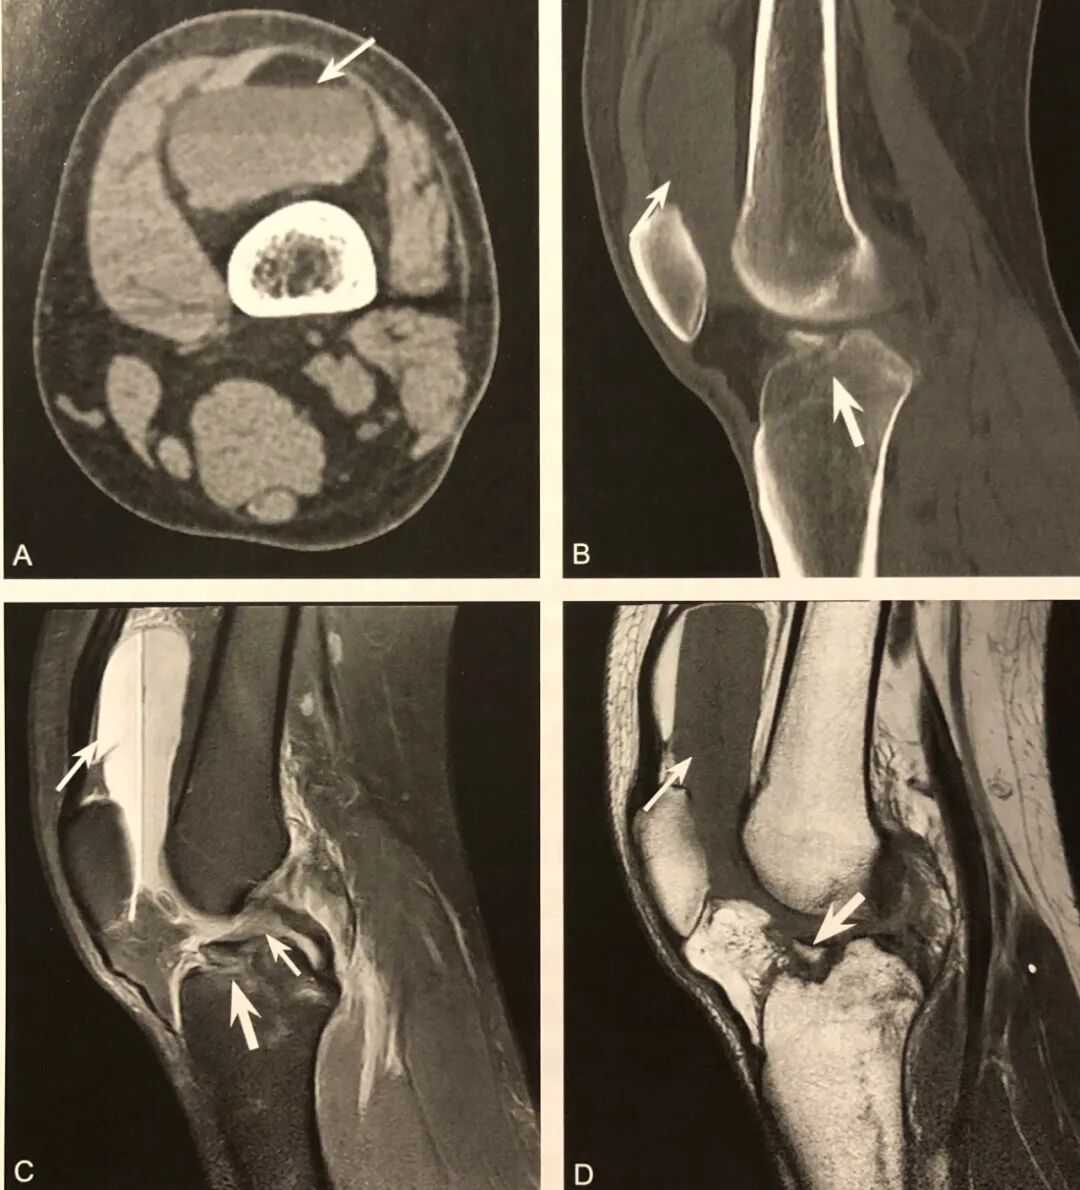

1. 腓骨小头撕脱性骨折的直接征象,弓形复合体和后外侧角损伤的间接征象;

2. 在膝关节X线前后位或 CT、MRI 冠状位观察,表现为近端腓骨小头或腓骨茎突撕脱性骨折,碎骨片呈弓形;

3. X 线片或 CT 观察到弓形征后,须行 MRI 检查,观察弓形复合体及后外侧角的完整性;

4. 少数后外侧角损伤合并腓总神经及胭动静脉损伤。